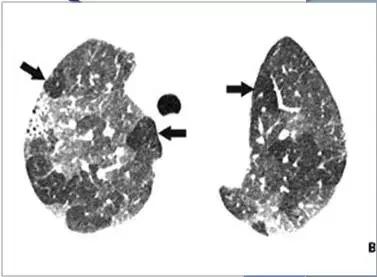

疾病:大叶干酪性肺炎

疾病:继发型肺结核

结核球厚壁空洞

大叶性肺实变:肺结核—大叶干酪肺炎-虫蚀空洞